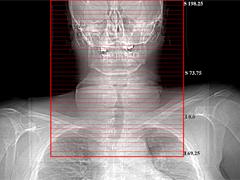

“We developed the first Image Wisely Radiation Safety Case to help imaging providers understand that the dose indices currently displayed on CT scanners CTDIvol (computed tomography dose index) and DLP (dose-length product) are not patient dose but are the dose to a standard phantom. To understand the dose to the patient better the Size Specific Dose Estimate (SSDE) has been developed,” said Donald Peck, Ph.D., and co-author of the first Image Wisely Radiation Safety Case.